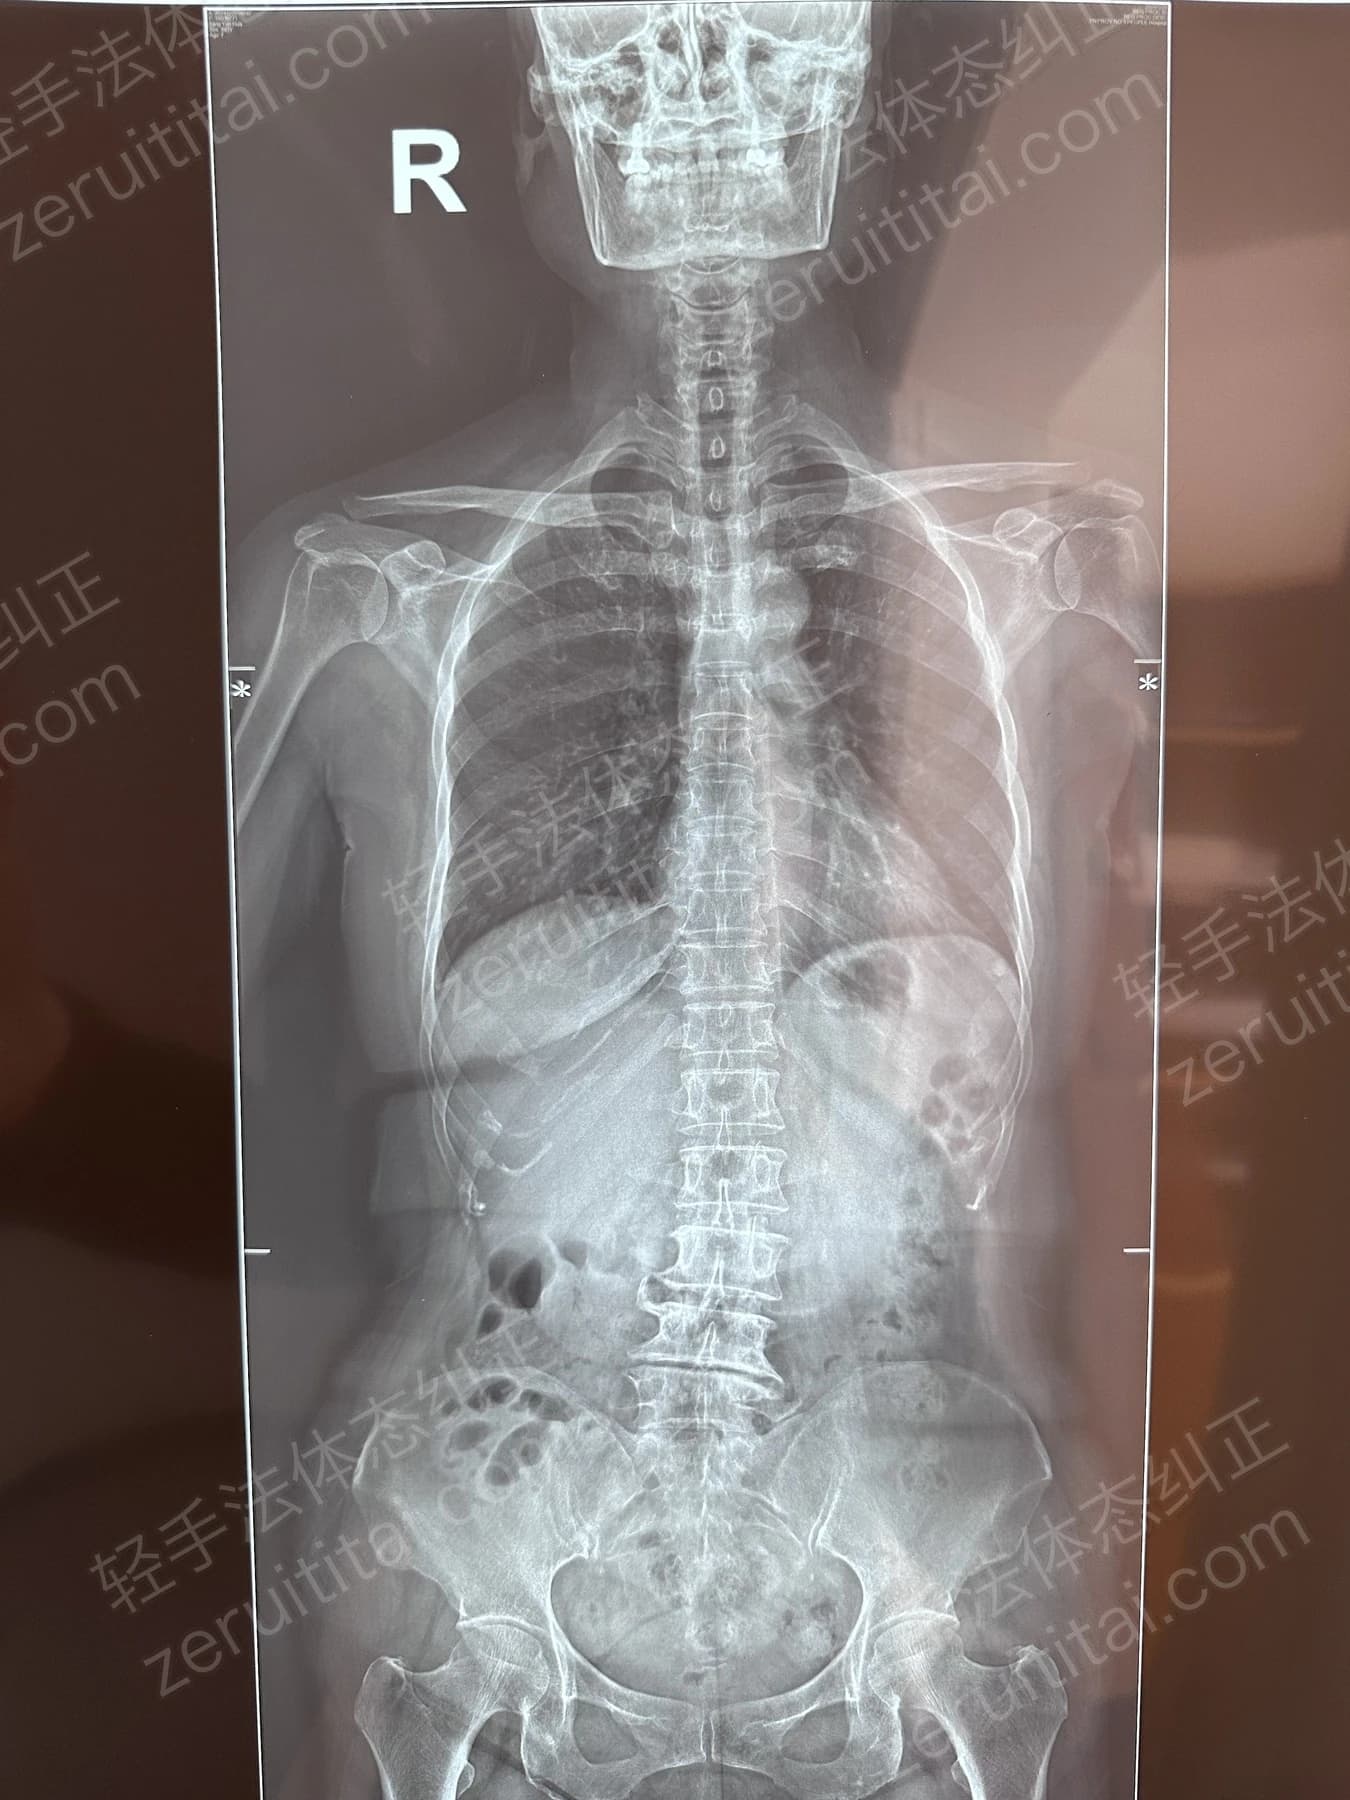

2022.06.27

第 1 次记录

第 1 次记录2022.06.27

正面 X 光